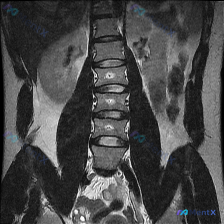

网上看到一份腰椎MRI T2序列冠状位的影像资料,先不贴报告结论,大家第一眼读片会怎么想? 目前已知的影像描述: - 脊柱冠状位呈现明显向右侧凸畸形,弯曲位于腰椎中段 - 腰椎椎体形态基本完整,未见楔形变或骨折;T2序列椎体骨髓信号大致均匀,未见局灶性高/低信号影 - 多处椎间隙非对称性改变,两侧高...